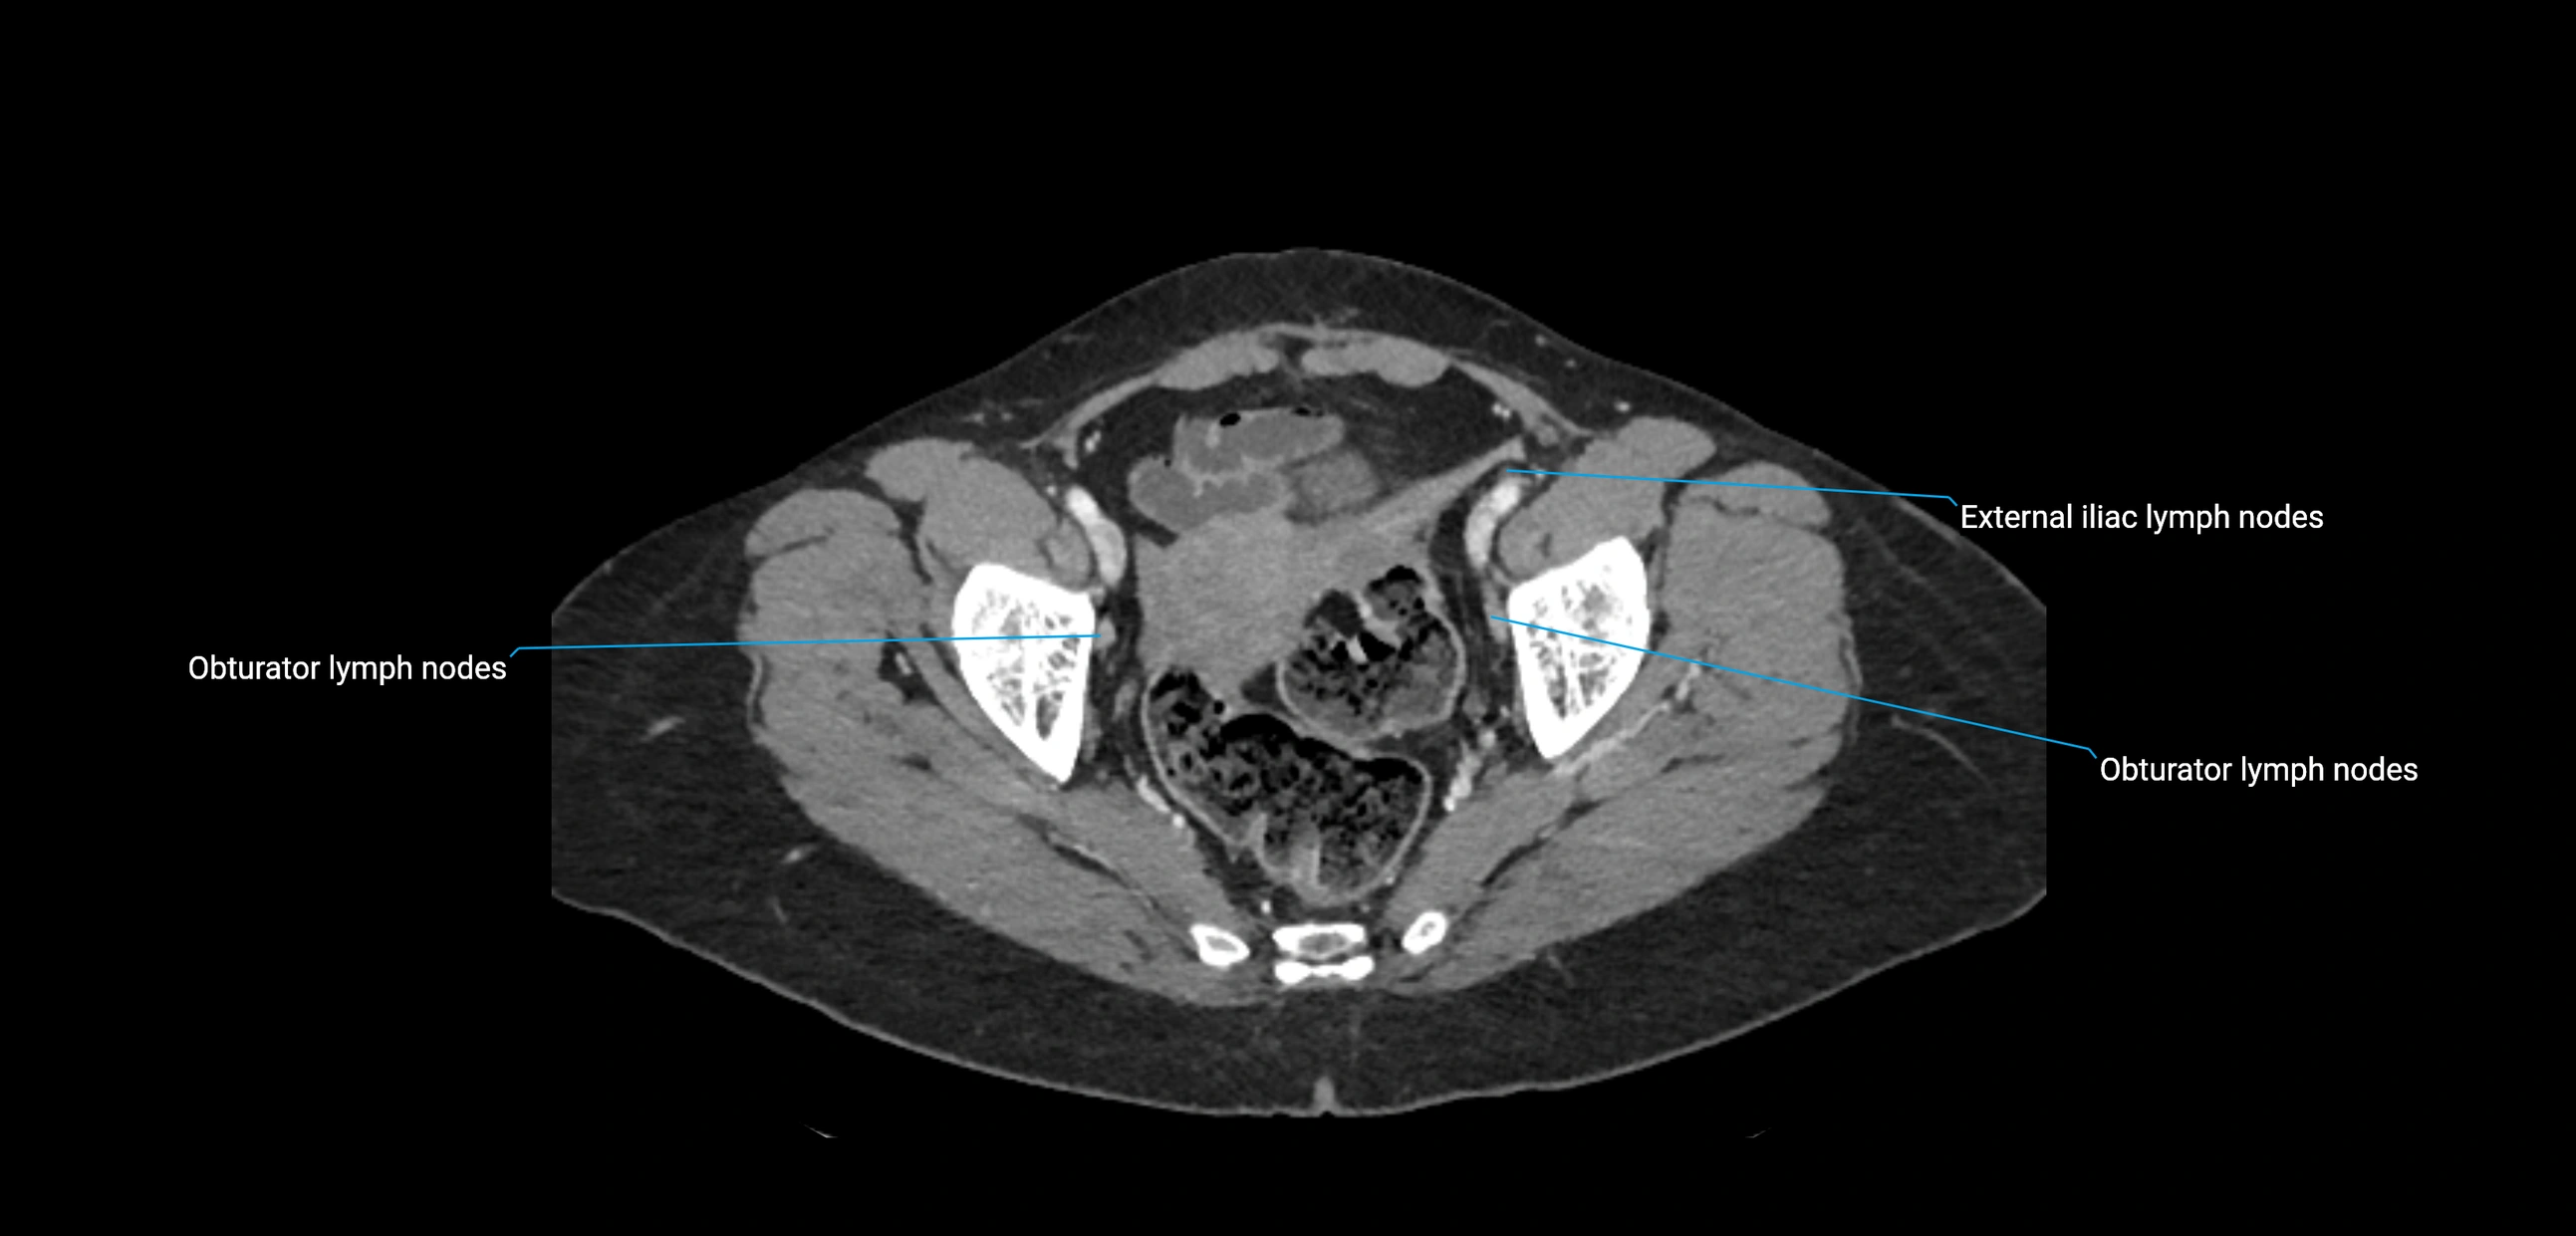

CT image

image